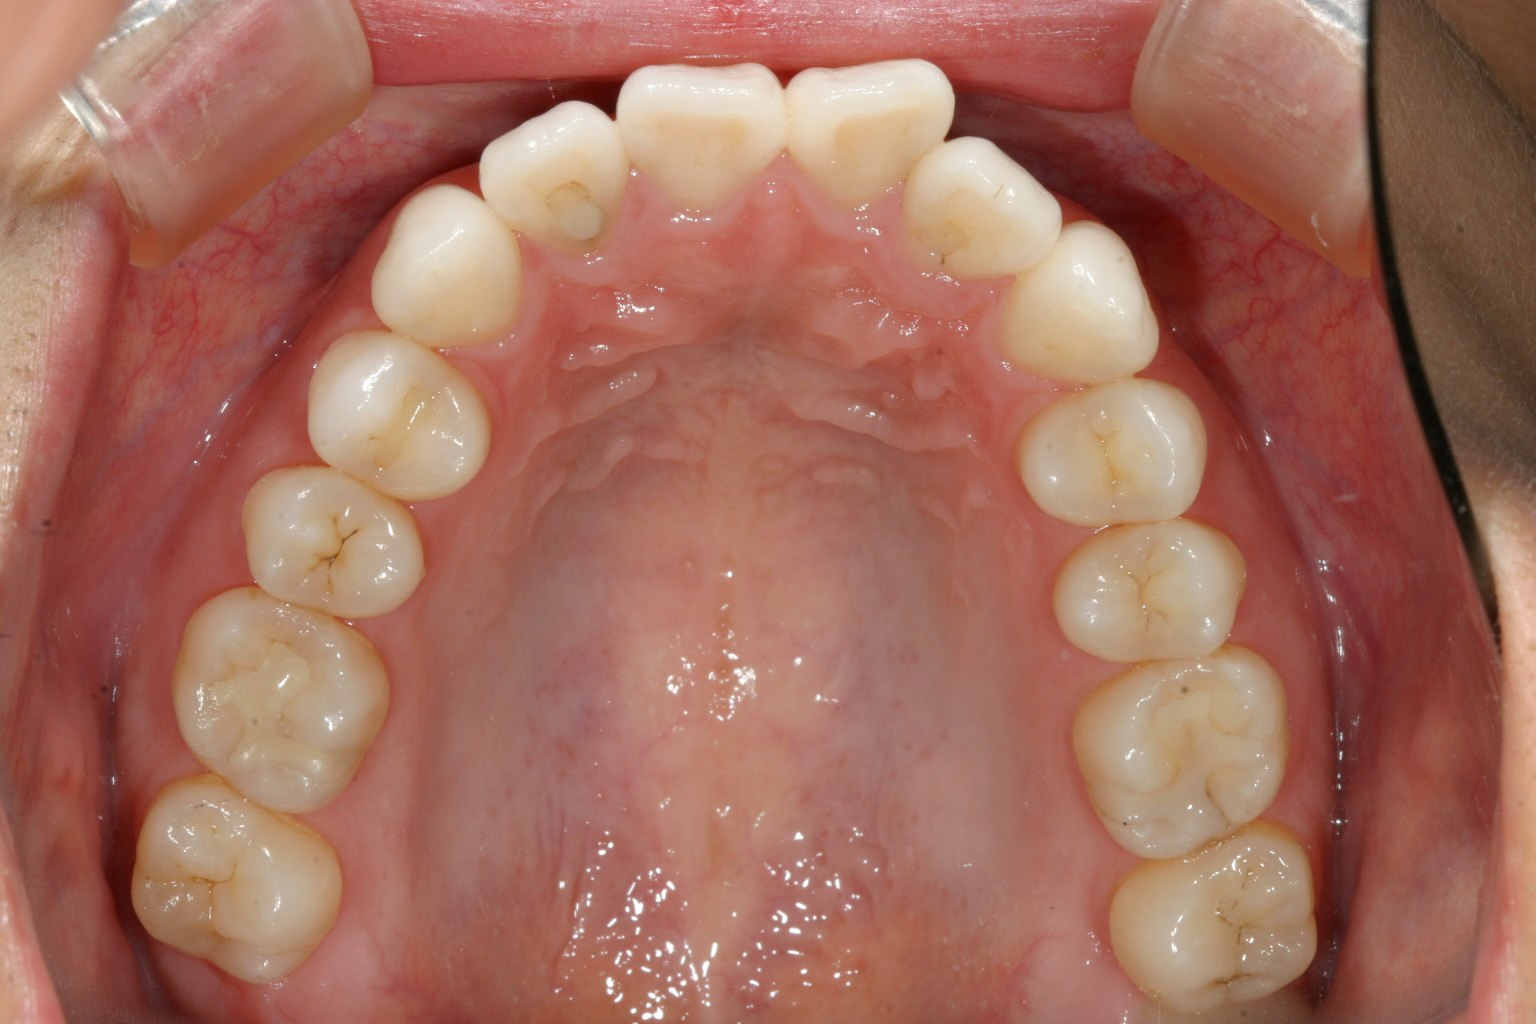

前歯が少し翼状捻転してます。

下顎小臼歯部が少しガタついてます。